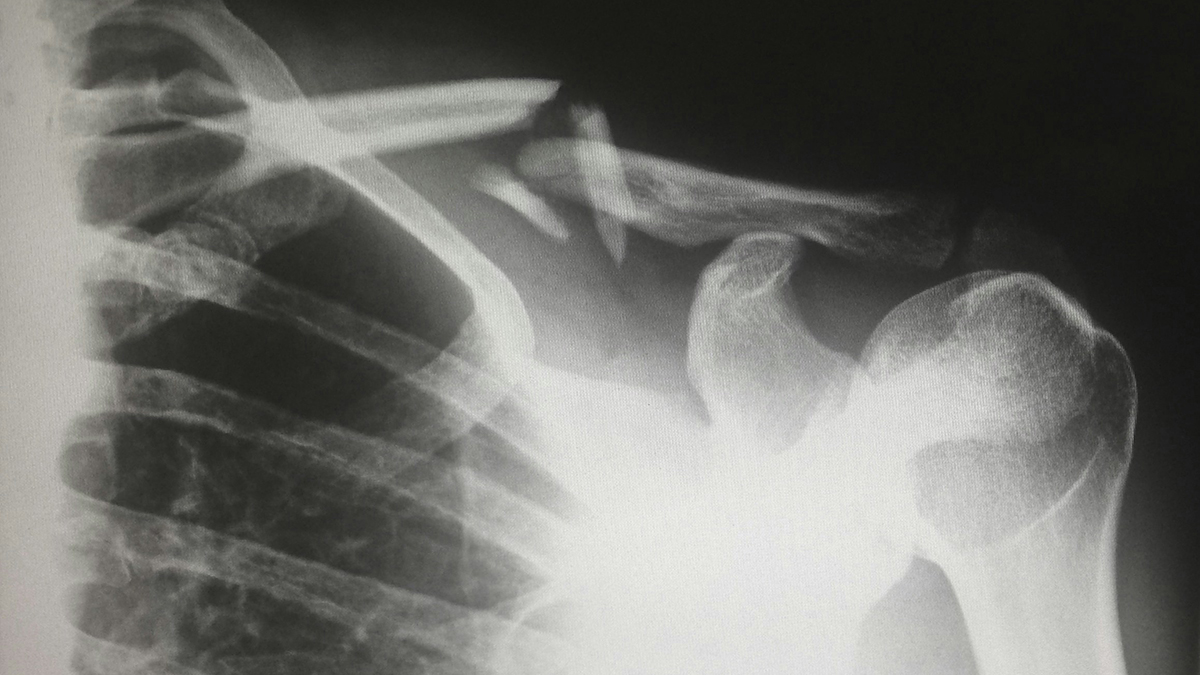

A study in Finland found that about 99% of adults over 40 have abnormalities in their shoulders seen in MRI scans. The research focused on people who reported shoulder pain or difficulty moving their arms. Interestingly, there is a weak connection between these MRI findings and actual pain or movement issues. This means that having abnormalities does not always mean a person will feel pain. This discovery may change how we think about shoulder health, especially since many older adults show these abnormalities.

フィンランドの研究によると、40歳以上の成人の約99%がMRI検査で肩に異常が見つかることがわかりました。この研究は、肩の痛みや腕の動かしにくさといった症状を訴える人々を対象に行われました。興味深いことに、MRIでの異常所見と実際の痛みや運動制限との関連は弱いことが示されています。つまり、肩に異常があっても、必ずしも痛みを伴うわけではないということです。この発見は、肩の健康に関する考え方を見直すきっかけになるかもしれません。特に、年齢とともに肩に異常が見つかることが多いことから、医療現場での診断や治療方針に影響を与える可能性があります。